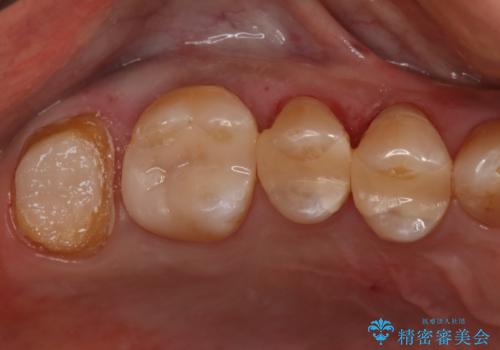

- かなり昔に入れた銀歯の部分のチェックをご希望でご来院されました。

上下ともに銀歯が多く入っており、その下に虫歯が疑われる状態でした。

詰め物の大きさや虫歯の状態から個々に材料と治療範囲を決定し治療に入りました。